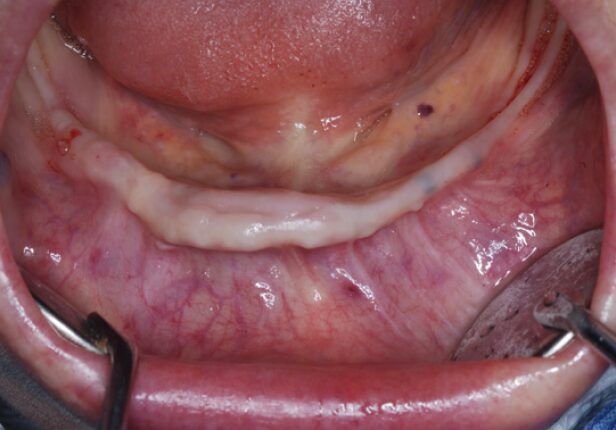

Mandibular Full case

Before surgery